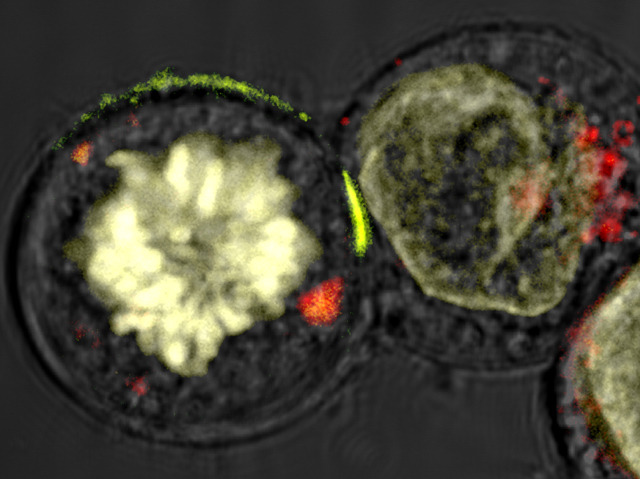

Patrolling our body, in search of diseased or foreign cells, is a crack squad of biological assassins known as natural killer (NK) cells. When they spot a sick cell, NK cells lock on, punch a hole and inject a payload of deadly enzyme-packed granules that kill within minutes. Using a new type of super-resolution microscope, and with laser ‘tweezers’ to manipulate the cells, researchers can now spy on the execution in greater detail than ever. Pictured is an NK cell (left) deciding whether its target cell (right) is dangerous. If deemed so, a ring-like tunnel will form (at the contact point dyed green) through which the toxic granules pass. NK cells play a prominent role in our immune system with duties that range from killing cancer cells to rejecting donor organs. In these scenarios, understanding the modus operandi of our natural killers is likely to aid development of new treatments.